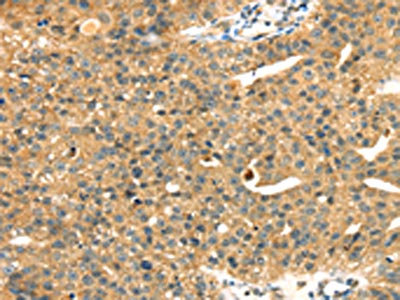

The image on the left is immunohistochemistry of paraffin-embedded Human liver cancer tissue using CSB-PA644665(MAPK12 Antibody) at dilution 1/25, on the right is treated with fusion protein. (Original magnification: ×200)